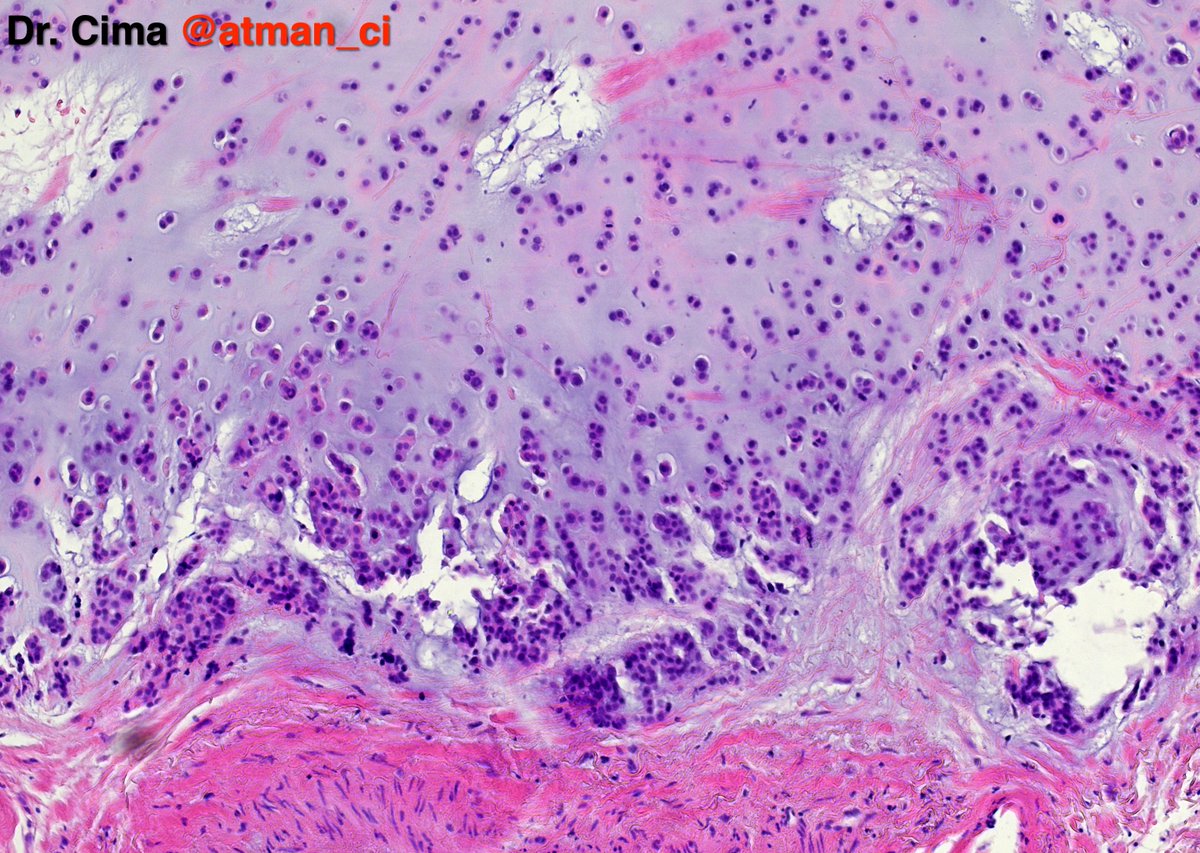

Hot off the press!! Check out this paper by Dr. Brandwein and team: Tall cell variant papillary thyroid carcinoma impacts disease-free survival at the 10 % cut-point on multivariate a… pubmed.ncbi.nlm.nih.gov/35834884/ #HeadAndNeckPath #ENTPath #ThyroidPath